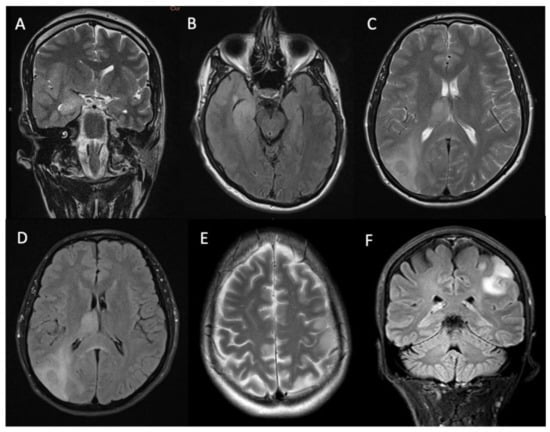

3.3. Imaging Characteristics

| Radiological characteristics | Numbers (percentage) |

| Contrast enhancement | |

| Solid pattern | 18 (33%) |

| Rim enhancement | 17 (31%) |

| Non-enhancing | 19 (36%) |